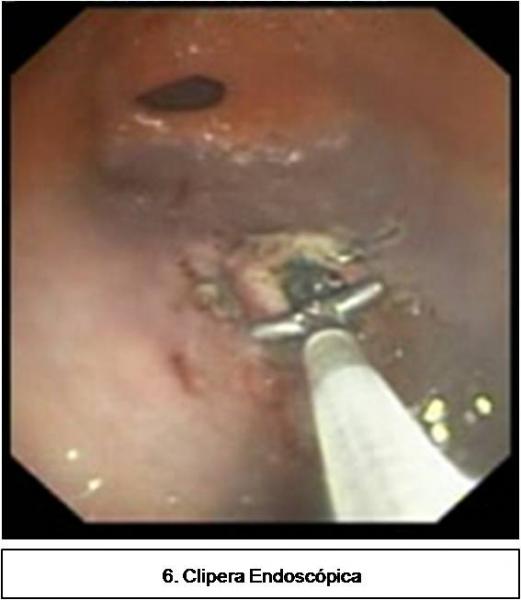

Isquemia mesentérica: Aguda y crónica